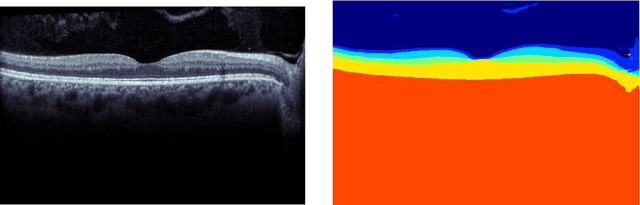

Abstract:Our objective is to evaluate the efficacy of methods that use deep learning (DL) for the automatic fine-grained segmentation of optical coherence tomography (OCT) images of the retina. OCT images from 10 patients with mild non-proliferative diabetic retinopathy were used from a public (U. of Miami) dataset. For each patient, five images were available: one image of the fovea center, two images of the perifovea, and two images of the parafovea. For each image, two expert graders each manually annotated five retinal surfaces (i.e. boundaries between pairs of retinal layers). The first grader's annotations were used as ground truth and the second grader's annotations to compute inter-operator agreement. The proposed automated approach segments images using fully convolutional networks (FCNs) together with Gaussian process (GP)-based regression as a post-processing step to improve the quality of the estimates. Using 10-fold cross validation, the performance of the algorithms is determined by computing the per-pixel unsigned error (distance) between the automated estimates and the ground truth annotations generated by the first manual grader. We compare the proposed method against five state of the art automatic segmentation techniques. The results show that the proposed methods compare favorably with state of the art techniques, resulting in the smallest mean unsigned error values and associated standard deviations, and performance is comparable with human annotation of retinal layers from OCT when there is only mild retinopathy. The results suggest that semantic segmentation using FCNs, coupled with regression-based post-processing, can effectively solve the OCT segmentation problem on par with human capabilities with mild retinopathy.